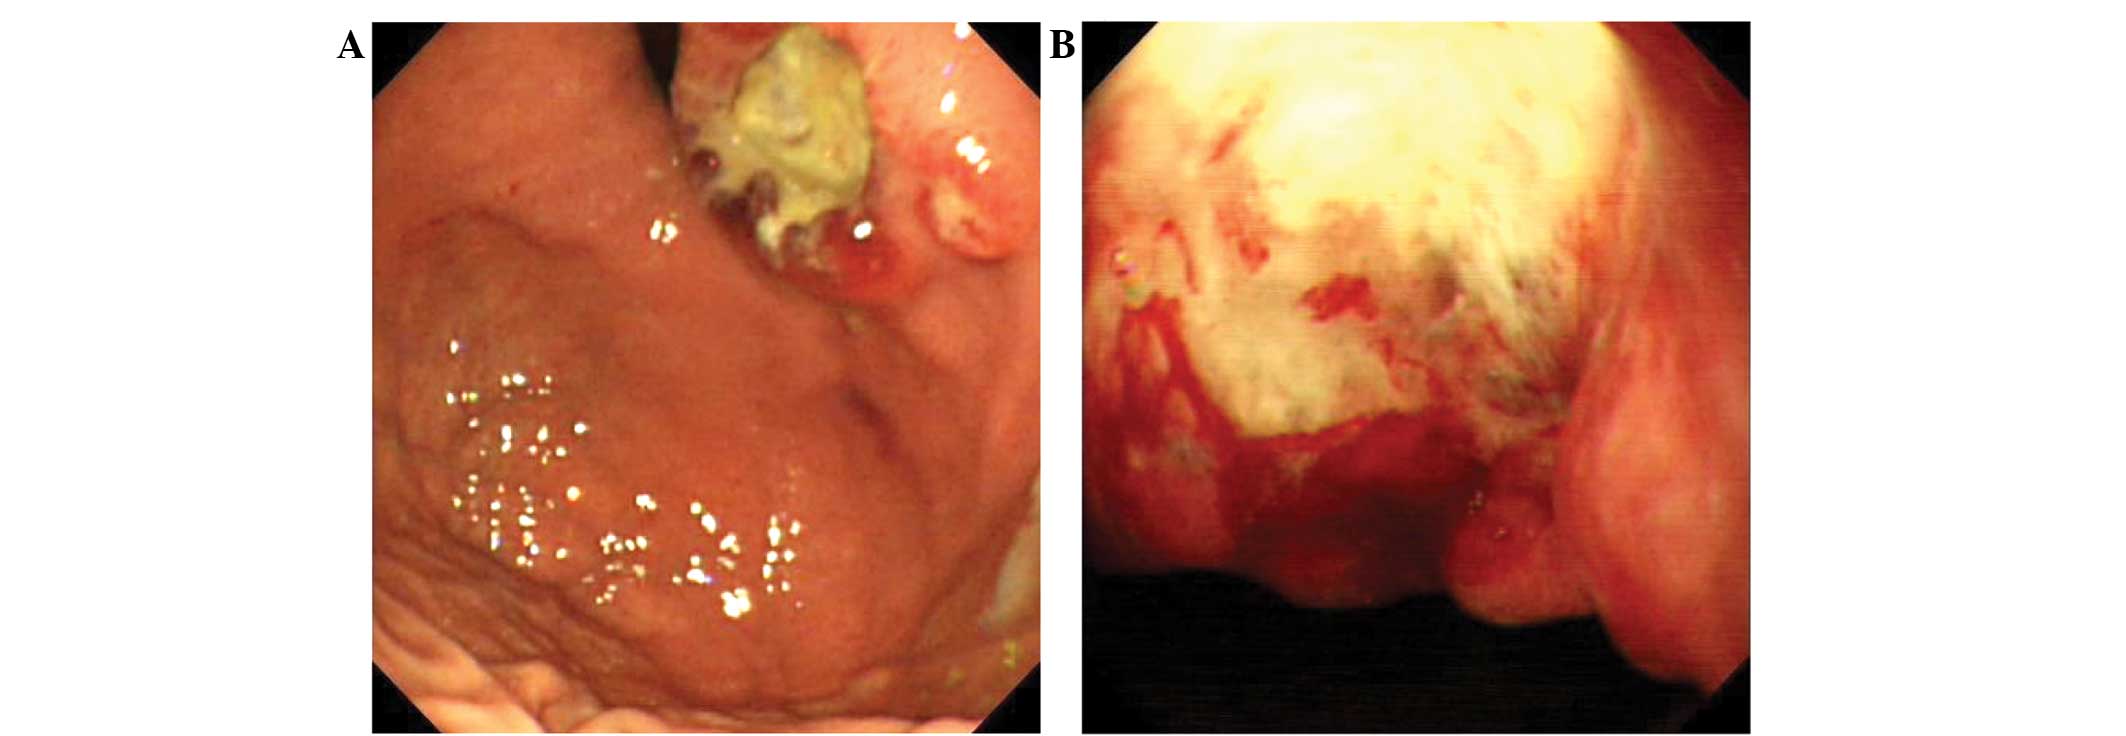

A 41-year-old woman presented to the First Affiliated Hospital of Dalian Medical University (Dalian, Liaoning, China) in January 2013, with a history of various clinical symptoms for 2 months, including epigastric pain and abdominal distention, which had been ongoing for two months. An endoscopic examination revealed an ulcer located in the cardia of the stomach, which was 4.0×3.5 cm in size (Fig. 1A and B). Following an endoscopic biopsy, an initial diagnosis of a poorly-differentiated adenocarcinoma was made. Subsequently, a total gastrectomy with regional lymph node dissection was performed. The resected ulcer was irregular in shape with raised edges and was covered with pale yellow exudates. The cut face of the ulcer was gray and solid, and the tumor infiltrated the whole wall of the stomach.

Figure 1.

Endoscopic features. (A) The ulcerative lesions were mainly observed in the cardia of the stomach. (B) The ulcer was covered with pale yellow exudates.